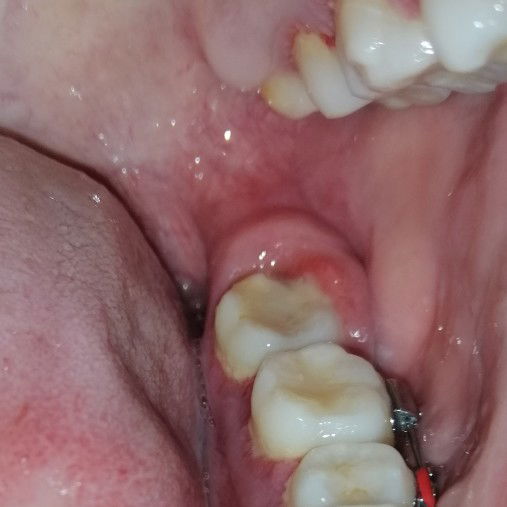

Swollen gums

Hi mommies. Ask ko lang kung ano kaya pwedeng remedy sa sobrang sakit at namamagang gums? Ang hirap kasi di pwedeng inuman ng pain killer while preggy. Di ako nakakatulog sa sobrang sakit di ako makakain at di ko masara mouth ko kasi namamaga siya. Dun pa sa part ng bagang ko pa. ??